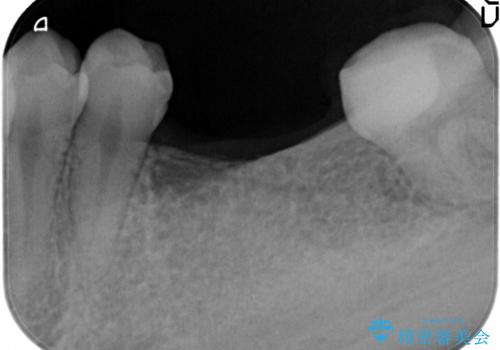

- 奥歯が二本欠損しており、その奥に親知らずが残っていました。

インプラントの一時手術と親知らずの抜歯を同時にしています。

親知らずはだいぶ後方にあり使うことが難しいため抜歯しています。